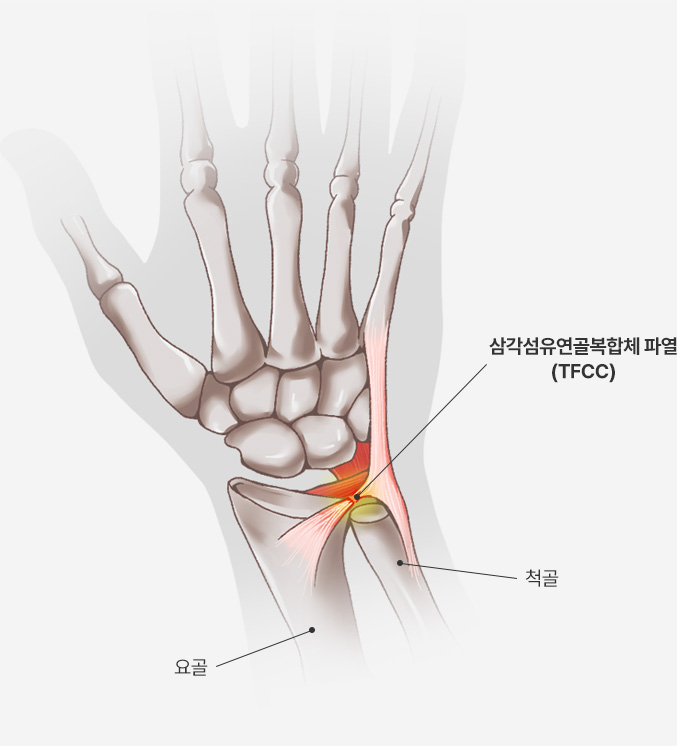

손목의 새끼손가락 쪽에 위치한 삼각형 모양의 연골 및 인대 복합체이며, 손목 관절의 안정성 유지 및 충격 흡수의 역할을 합니다.

또한 요골과 척골 사이의 움직임을 조절하고, 손목의 회전 운동을 보조합니다.

삼각섬유연골복합체 파열이 있을 경우 MRI 에서 다음과 같이 뼈 부착부에서의 파열(빨간 원)과